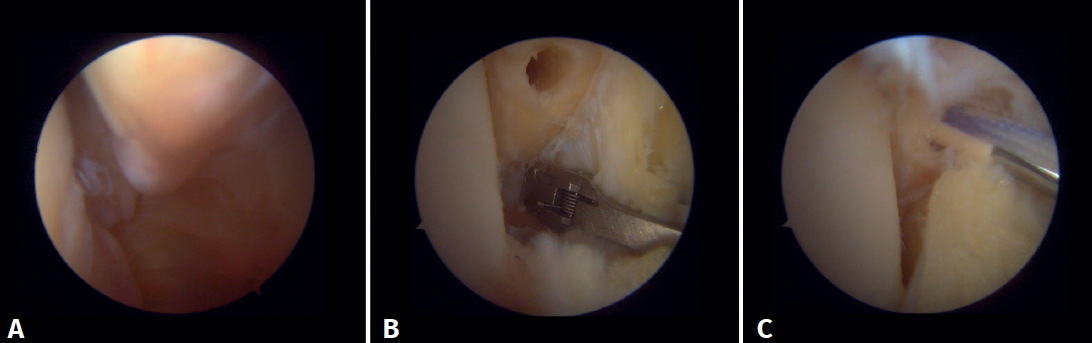

En cuanto a la técnica quirúrgica, los portales de trabajo se realizarán de la misma manera que en una artroscopia de tobillo convencional: un portal anteromedial y uno anterolateral. Se inicia siempre con una artroscopia diagnóstica para confirmar la lesión del ligamento deltoideo. Puede utilizarse un palpador para verificar la laxitud de las fibras y realizar una prueba con este introduciéndolo a través de la gotera medial: si pasa, confirma la lesión. Para la reparación, el portal de visión será el anterolateral, así se trabajará de forma más directa a través del anteromedial. Las fibras anteriores del tibiotalar superficial e intermedias de la porción profunda del deltoideo son las que la técnica artroscópica permite reparar(38). Una vez identificado y disecado el ligamento, se pasa una sutura entre las fibras mediante un pasador de sutura. Se prepara la zona de anclaje del maléolo medial con un rasurador o una pequeña fresa. Con el tobillo en posición neutra se introduce el ancla manteniendo la tensión de las suturas. Se puede utilizar como referencia anatómica para la colocación la intersección de la línea paralela a la articulación tibiotalar y una línea perpendicular marcada desde la punta del maléolo y por el borde lateral de este(21). Tras realizar la reducción, se prueba nuevamente la tensión de las fibras y el paso del probador por la gotera medial, que confirma una adecuada reparación (Figura 8).

Figura 7. A: desbridamiento del espacio tibioperoneo; B: estabilización de la sindesmosis mediante sistema de suspensión.